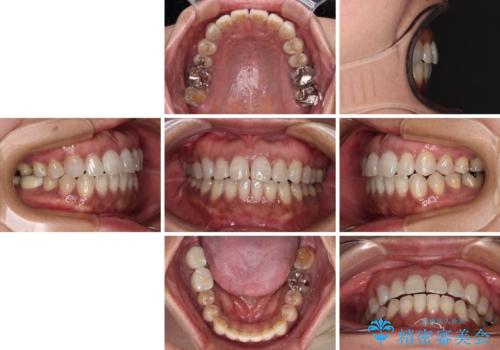

極端な上下前歯の開咬を改善 オープンバイトのインビザライン矯正

- 上下前歯の隙間を気にして来院された患者様です。

開咬の治療は、前歯を閉じるように動かすとともに、上下臼歯を圧下(骨内にめり込ませる)させることで進めて行きます。

インビザラインは臼歯の圧下を効果的に行えるため、インビザラインを用いて矯正治療を行うこととしました。

治療前に、いくらインビザライン矯正がオープンバイトを得意としているとは言え、さすがに限界があるだろうと思っておりましたが、前歯でレタスが噛めるまで改善することができました。

顔の印象も大きく変わり、患者様には大変満足していただきました。